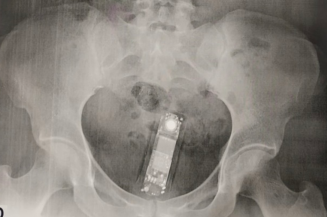

Foto: Reprodução

Policial

Mulher foi presa ao tentar entrar com aparelhos celulares, introduzidos em seu corpo no presídio estadual de Formosa

Por volta das 12h desta quinta-feira (24/10), uma equipe da Polícia Militar deslocaram-se até o Presídio Estad...